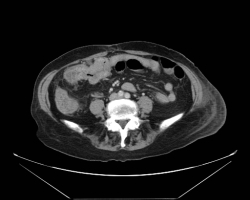

Les syndromes occlusifs, définis par l’arrêt complet du transit intestinal, regroupent quatre signes cliniques élémentaires : l’arrêt des matières et des gaz, les vomissements, la douleur et le météorisme abdominal, d’expression variable selon l’étiologie. […]